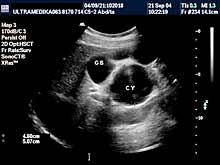

Posebni pregledi:

- Mogu biti nastavljeni nakon standardnog pregleda ako

zato postoje indikacije, ili

- postoje razlozi koji indikuju odmah

poseban pregled!

- Fokalne promene jetre, pankreasa i ostalih parenhimatoznih organa (3D

Sono CT procena i procena vaskularizacije sa Broad band-CD i PD i 3D

CPA modom).

- 3D Sono CT žučne kese i žučnih i pankreasnih puteva.